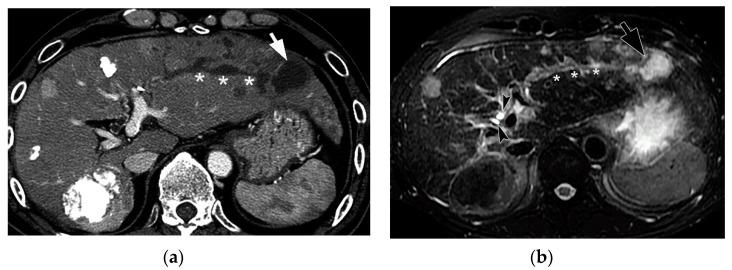

Bile duct necrosis (BDN) with biloma formation is a type of ischemic bile duct injury that is one of the serious complications associated with transarterial therapies, such as transcatheter chemoembolization therapy (TACE), and radioembolization for hepatocellular carcinoma (HCC) and hepatic arterial infusion chemotherapy (HAIC) for metastatic liver cancer from colorectal carcinoma. In terms of the occurrence of BDN and subsequent biloma formation, ischemic injury to the peribiliary vascular plexus (PBP), the supporting vessel of bile duct epithelium, is thought to be intimately associated. In this paper, we first describe the anatomy, blood supply, and function of the intrahepatic bile duct, and then illustrate the pathophysiology of BDN, and finally present the imaging findings of BDN. Under the process of BDN formation, ischemia of the PBP induces the disruption of the bile duct epithelial protection mechanism that causes coagulation and fibrinoid necrosis of the surrounding tissue by the detergent action of exuded bile acids, and eventually a biloma forms. Once BDN occurs, persistent tissue damage to the surrounding bile duct is induced by imbibed bile acids, and portal vein thrombosis may also be observed. On pre-contrast and contrast-enhanced computed tomography (CT), BDN shows similar findings to intrahepatic bile duct dilatation, and, therefore, it is sometimes misdiagnosed. Differentiation of imaging findings on CT and ultrasound (US)/magnetic resonance (MR) imaging/MR cholangiopancreatography (MRCP) is important for correct diagnosis of BDN.

伴有胆汁瘤形成的胆管坏死(BDN)是一种缺血性胆管损伤,是经动脉治疗相关的严重并发症之一,如经导管肝动脉化疗栓塞术(TACE)、肝细胞癌(HCC)的放射性栓塞以及结直肠癌肝转移的肝动脉灌注化疗(HAIC)。就BDN的发生及随后胆汁瘤的形成而言,胆管周围血管丛(PBP)(胆管上皮的支持血管)的缺血性损伤被认为与之密切相关。在本文中,我们首先描述肝内胆管的解剖结构、血液供应和功能,然后阐述BDN的病理生理学,最后介绍BDN的影像学表现。在BDN形成过程中,PBP的缺血会导致胆管上皮保护机制的破坏,渗出的胆汁酸通过去污剂作用导致周围组织发生凝固性坏死和纤维蛋白样坏死,最终形成胆汁瘤。一旦发生BDN,吸收的胆汁酸会导致周围胆管持续的组织损伤,还可能观察到门静脉血栓形成。在平扫及增强计算机断层扫描(CT)上,BDN表现与肝内胆管扩张相似,因此有时会被误诊。CT及超声(US)/磁共振(MR)成像/磁共振胰胆管造影(MRCP)上影像学表现的鉴别对于BDN的正确诊断很重要。